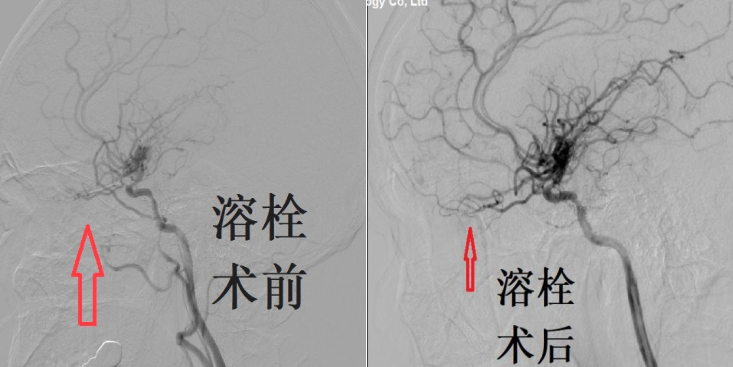

眼动脉超选择动脉溶栓术前术后对比

入院后,神经介入外科联合眼科于湛主任团队会诊,确诊为患者双眼视网膜中央动脉阻塞,双眼完全失明。多学科团队多次讨论,结合患者病情,重点考虑患者发病时间较长的因素,最后讨论后决定,为患者行局麻下双侧眼动脉超选择溶栓治疗。

近年来,介入技术不断发展,超选择动脉溶栓逐渐应用于视网膜中央动脉阻塞治疗,该方法将溶栓药物直接注射到患者的眼动脉内,溶栓效果好,并发症少,该治疗方法有效率为34.8%,高于该病的自然病程及传统治疗的视力恢复。